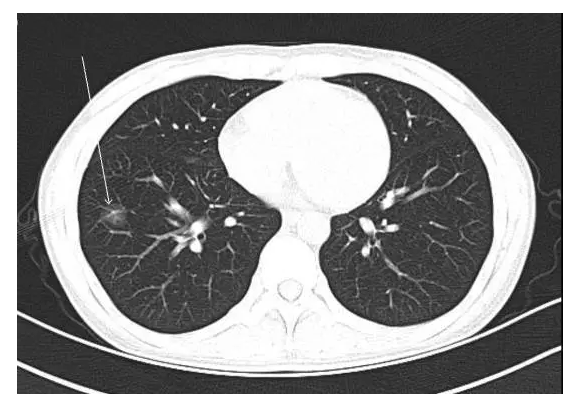

朱國清教授:首先必須分清結(jié)節(jié)的性質(zhì),若是單純的磨玻璃結(jié)節(jié)(簡稱ggo),不必太過慌張。磨玻璃結(jié)節(jié)與良性病變、癌前期病變都可能有關(guān)系。如果是純磨玻璃結(jié)節(jié),直徑小于5毫米的,一年后復(fù)查,觀察結(jié)節(jié)大小有無變化;直徑在5到10毫米之間的,半年后復(fù)查;如果直徑大于10毫米,則3到6個月就要密切觀察。隨訪期間假如發(fā)現(xiàn)結(jié)節(jié)增大,則可以考慮手術(shù)切除。

一般來說,純磨玻璃結(jié)節(jié)的變化是非常緩慢的,它是一種惰性疾病。有的患者過度緊張,要求醫(yī)生必須趕快開掉,其實大可不必。純磨玻璃結(jié)節(jié)還有一個特點就是亞洲人多、女性多、不吸煙人的多。日本和韓國對此都做過流行病學調(diào)查,韓國的調(diào)查結(jié)果是,五年時間里,只有9.8%的純磨玻璃結(jié)節(jié)發(fā)生了變化,而這些輕微出現(xiàn)變化的患者進行手術(shù)后也能得到治愈。日本的數(shù)據(jù)也與韓國類似。

所以,對于純磨玻璃小結(jié)節(jié)可以靜觀其變,但如果結(jié)節(jié)是實性的,尤其是大于8毫米的,就不能這么淡定了,需要迅速應(yīng)對,請醫(yī)生進行判斷,假如高度懷疑肺癌的,應(yīng)該考慮盡快手術(shù)。